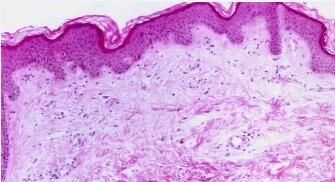

1. 慢性荨麻疹目前是一种常找不到较好病因的病症,患者常常不定时地在脸颊或四肢出现一块块红肿且痒痛的皮疹,往往越抓越觉的痒。在日常的生活中应多吃蔬菜和水果。以促使此病的缓解。